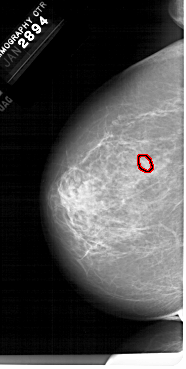

A_1679_1.LEFT_CC

LEFT_CC LINES 6631 PIXELS_PER_LINE 3346 BITS_PER_PIXEL 12 RESOLUTION 43.5 OVERLAY

FILE: A_1679_1.LEFT_CC.OVERLAY

TOTAL_ABNORMALITIES 1

ABNORMALITY 1

LESION_TYPE MASS SHAPE LOBULATED MARGINS OBSCURED-CIRCUMSCRIBED

ASSESSMENT 4

SUBTLETY 3

PATHOLOGY BENIGN

TOTAL_OUTLINES 1

BOUNDARY